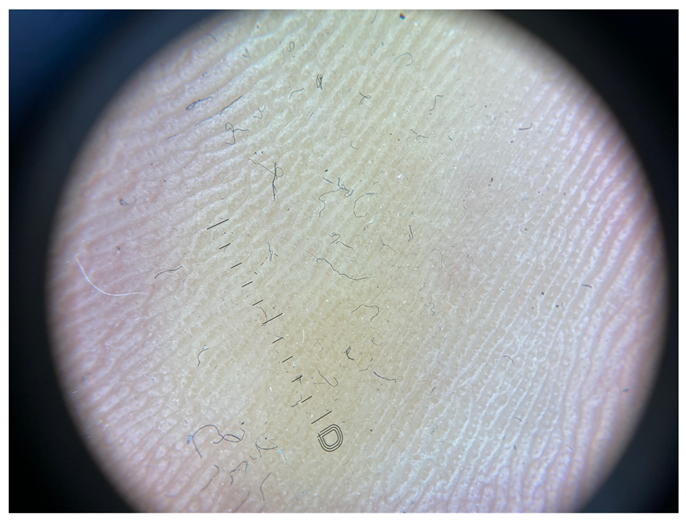

| Grade | Dermoscopic View |

|---|---|

| Grade I | Foto Finder dermatoscopy, cross-polarization |

![]() | |

| DL-5 dermatoscopy, cross-polarization | |

| DL-5 dermatoscopy, parallel polarization | |